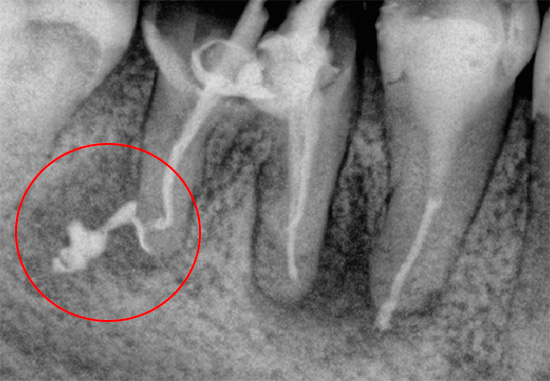

Un dente che è stato a lungo sigillato nei canali con un riempimento sigillato di alta qualità di solito non dà fastidio se non si sono verificati errori durante il trattamento. Se il vecchio sigillo cessa di soddisfare i requisiti di tenuta, o addirittura vola in pezzi, allora un dente morto inizia a ferire a causa dell'infezione nei canali già sigillati. Inoltre, durante il trattamento potrebbero essere commessi errori: un canale sigillato in modo incompleto con un'infezione rimasta al suo interno, uno strumento dentale rotto nel canale, ecc. Tutto ciò può anche causare infiammazione alla radice del dente e dolore nel tempo.

Le complicazioni durante e dopo il trattamento dei canali sono spesso provocate dal dentista a causa della scarsa formazione, mancanza di esperienza o attrezzature e materiali nella clinica. Molto spesso, il dolore dopo aver riempito i canali si verifica per i seguenti motivi:

- con eccessiva rimozione di materiale di riempimento oltre la radice;

- quando si salta un canale o canali in un dente;

- con scarsa elaborazione del canale;

- a causa di violazioni durante il passaggio e l'espansione di strumenti intra-canale;

- a causa del riempimento scadente;

- a causa di allergie al materiale di riempimento;

E altri

Nella maggior parte dei casi clinici, dopo aver eliminato l'errore commesso durante il trattamento, il dolore al dente o alla gomma circostante scompare rapidamente.